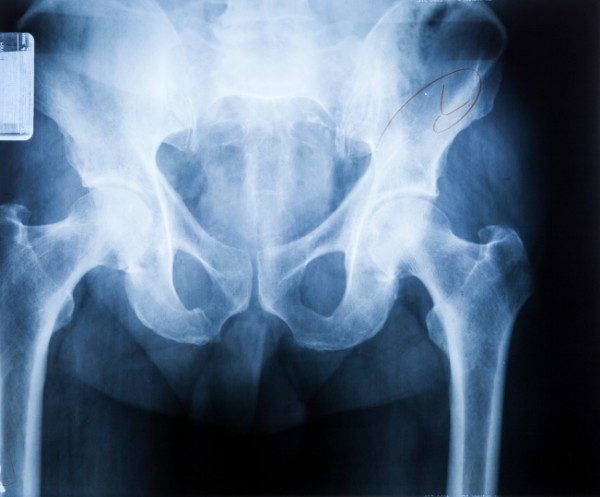

La sindrome dell’anca a scatto si può manifestare anche nei bambini, ma in genere non comporta problemi ulteriori, rischi o dolore. Si tratta di una condizione in cui si sente un vero e proprio scatto (anche con rumore) ad un semplice movimento dell’articolzione dell’anca, come quando ad esempio ci si siede o ci si alza, ma anche quando si cammina o corre. Di solito si parla di anca a scatto interna quando il disturbo origina internamente al giunto o esterna (al contrario). Spesso migliora con il riposo. Ma vediamo nel dettaglio.